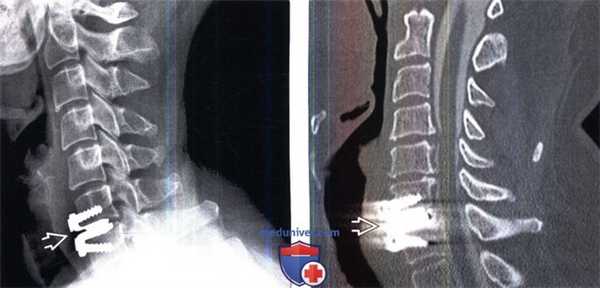

(Слева) Рентгенография шейного отдела позвоночника: протез межпозвонкового диска Bryan, состоящий из двух имеющих форму раковин [моллюсков] замыкательных пластинок, изготовленных из титана с пористым покрытием, и поликарбонат-полиэтиленового вкладыша. Этот протез отличается эластичными и амортизационными свойствами, обеспечивая свободные движения на уровне оперированного сегмента. Возможные осложнения включают переднюю или заднюю дислокацию компонентов протеза, кифотическую деформацию замыкательных пластинок и ограничение движений.

(Справа) Сагиттальный срез, Т1-ВИ, пациент с протезом Bryan межпозвонкового диска С5-С6. Протез характеризуется минимально выраженными артефактами магнитной восприимчивости.